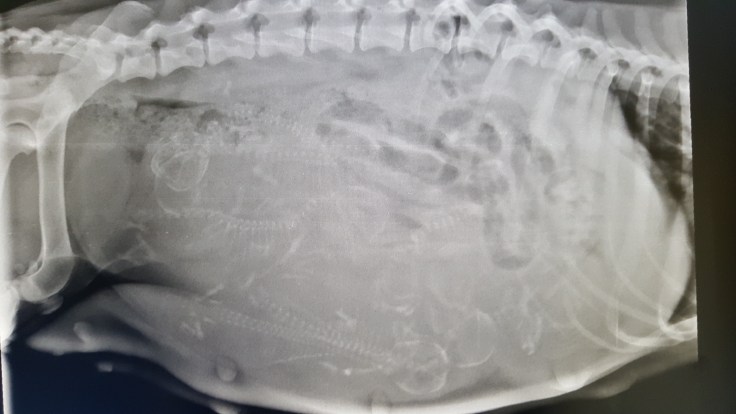

Heute waren wir mit Jalinaar beim lang ersehnten röntgen. Wir konnten SICHER 7 Welpen zählen, allerdings war auch nicht sichtbar was sich hinter den Darmschlingen so versteckt. Vielleicht erleben wir ja noch eine kleine Überraschung – wenn es dann doch 8 sind 😉